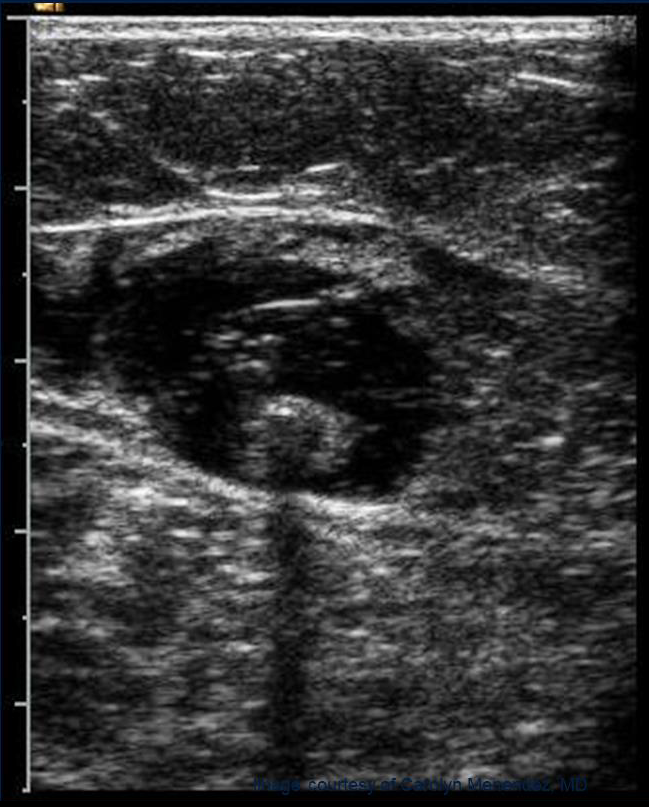

• Контрольное УЗИ через 72 часа для исключения тромбоза глубоких вен

• Периодическое УЗДГ вен нижних конечностей

РЕГЛАМЕНТ ПОСЛЕОПЕРАЦИОННОГО КОНТРОЛЯ (УЗИ)

• 24-72 часа - соустье

• 1-2 недели - ранняя реканализация

• 2 месяца - рубец

• 6 месяцев - отсутствует

• ежегодно - рецидив, другие венозные бассейны